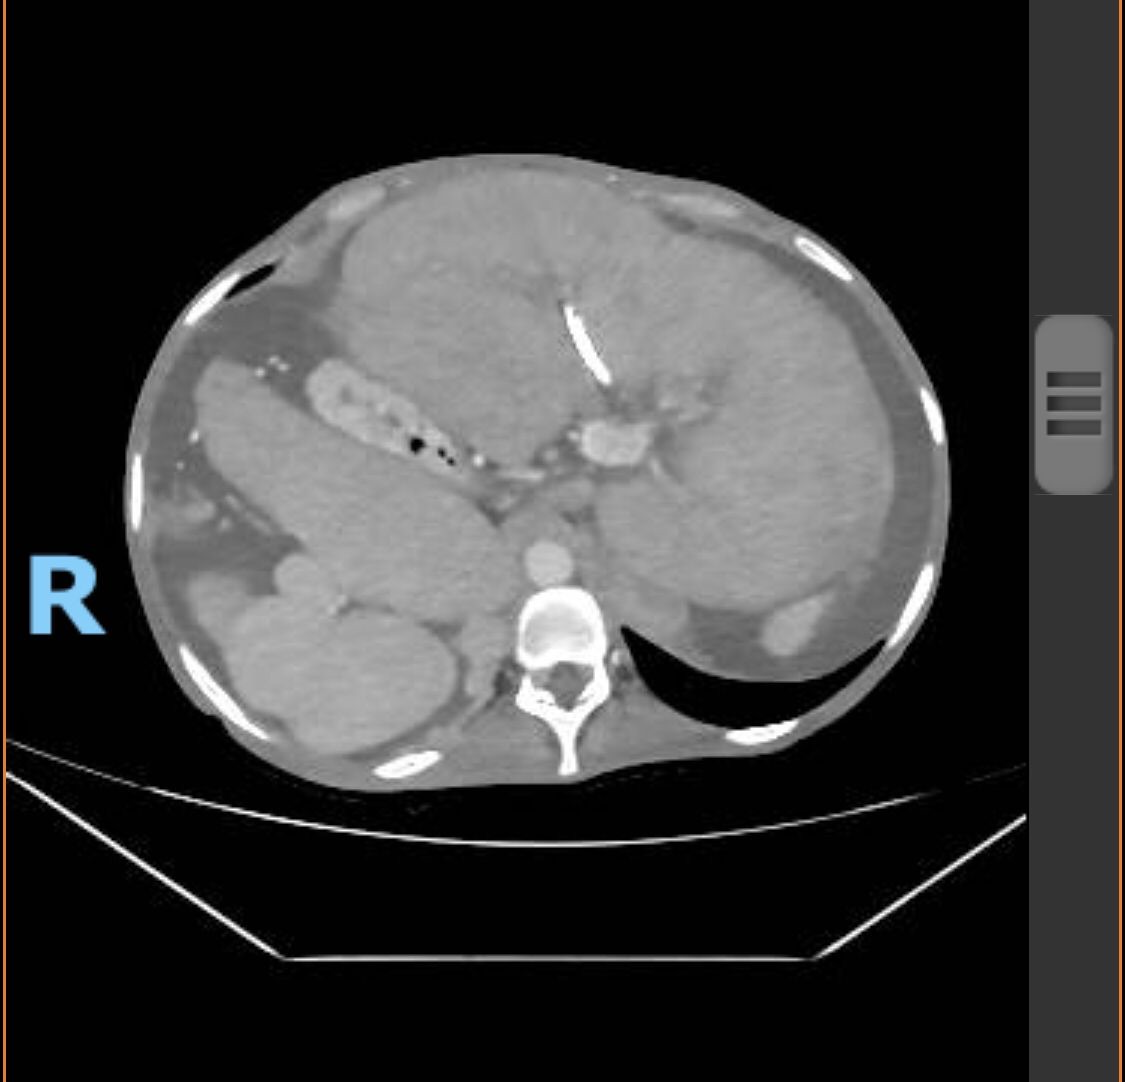

A 22-year-old man with situs inversus totalis and end-stage liver disease secondary to congenital biliary atresia and previous Kasai portoenterostomy at two months who was referred to our center with portal hypertensive bleeding, recurrent cholangitis, and hepatocellular carcinoma. He completed the liver transplant protocol. Preoperative liver angiotomography revealed, besides the mirror image orientation of the viscera and dextrocardia, inferior vena cava (IVC) and portal vein (PV) with good patency, splenorenal shunt, collateral circulation, and common hepatic artery arising from the superior mesenteric artery. A suitable 59-year-old cadaveric male donor with no anatomic variation was accepted. He underwent to liver transplant, his BMI was 16.7kg/m2, MELD and Child-Pugh scores were 24 and 7 points. The donor's liver weighed 1725g.

A bilateral subcostal incision was made; after extensive lysis of adhesions, the hepatectomy was performed with preservation of the recipient's IVC. The donor's liver was placed on the left side rotated 90º clockwis; this allowed perfect alignment of the recipient and dolor hila. The donor infrahepatic vena cava was anastomosed end-to-side to recipient IVC previous closing of the suprahepatic vena cava. The artery and PV were anastomosed end-to-end without vessel grafts. A choledocojejunostomy was performed using the previous Roux-en-Y. The patient had satisfactory evolution and was discharged on the 8th postoperative day with normal liver function.